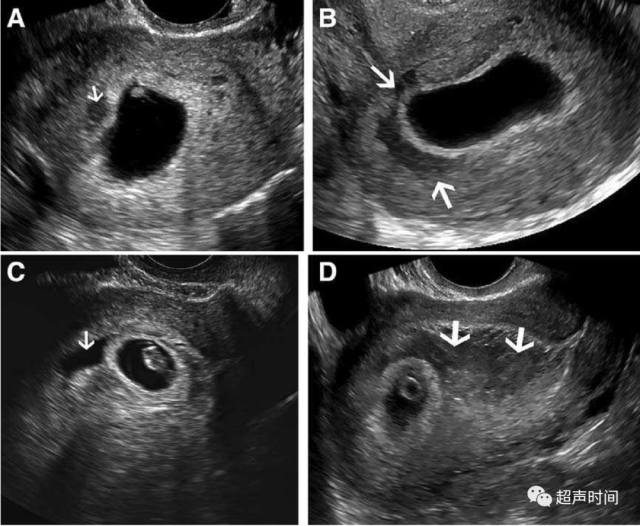

孕早期绒毛膜下血肿 超声评估方法和妊娠预后 丁香园